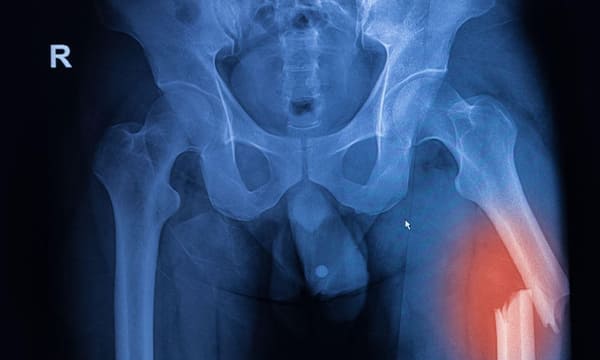

Intramedullary Nailing (IM Nailing) is a stabilisation technique used for fractures of long bones, such as the femur, tibia, and humerus. At Melbourne Orthopaedic Clinic, our team uses this advanced method to provide patients with strong, internal support that promotes bone healing and allows early mobility. This procedure is effective for treating fractures with minimal soft tissue disruption.

Intramedullary Nailing involves inserting a metal rod, or nail, into the central cavity of a long bone (the medullary canal). The nail is designed to keep fractured bone segments aligned and stable during healing. Once placed within the bone, the nail is secured with locking screws at each end to hold the fragments in place.

• Long Bone Fractures: Especially fractures of the femur (thigh bone), tibia (shin bone), and humerus (upper arm bone).